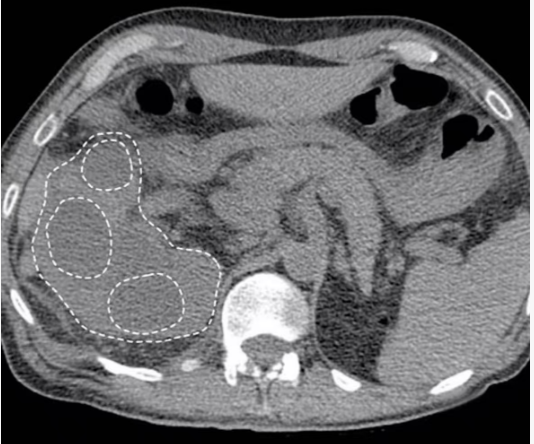

"熊掌征"(bear paw sign)是指在断面影像上肾盂粘连收缩,而肾盏扩张,肾皮质变薄,扩张的肾盏形似熊脚掌的征象,它是黄色肉芽肿性肾盂肾炎的一个重要特征性征象。

"熊掌征"表现为以肾盂肾盏为中心肾实质内多发囊性占位,其中部分囊为结石梗阻所致的肾积水,部分为黄色肉芽肿的脓腔;通常肾盏扩张为主,肾盂扩张常常不显,增强后,病变实性部分均匀强化,坏死区无强化,低密度区边缘环形强化。患肾体积增大或局限性隆起。常常伴有集合系统结石;肾皮质变薄;肾窦脂肪组织减少,多为慢性炎性反应性纤维组织增生所替代;肾周筋膜增厚、肾周间隙渗出积液,严重时可形成脓肿累及腰大肌。腹部X线平片典型的表现是受累的肾脏增大并有鹿角状结石,同侧腰大肌边缘模糊。超声显示肾脏轮廓变形,正常结构消失,中央可探及结石声影。